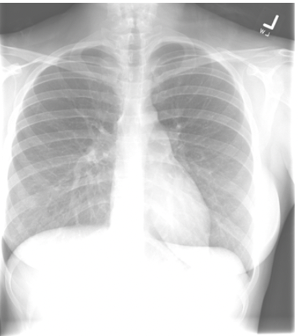

Scapulae in PA CXR:

A

How can the scapulae determine if a CXR is PA or AP?

PA → scapulae retracted laterally so do not overlap lungs

AP → scapulae not retracted laterally so remain projected over the lung